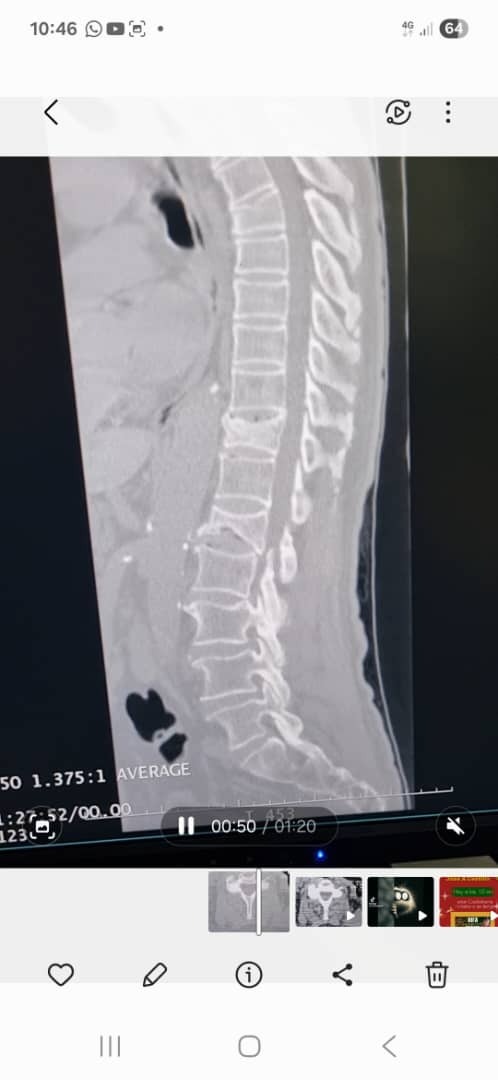

Luego de varias evaluaciones médicas y demoras en la atención, finalmente el 13 de noviembre fue evaluado por un neurocirujano en el Hospital Luis Gómez López. Tras realizar una tomografía, fue diagnosticado con fracturas por aplastamiento en las vértebras T11 y L1.

Ante este diagnóstico, se indicó la realización urgente de una vertebroplastia percutánea en ambos niveles, procedimiento necesario para aliviar su dolor y evitar mayores complicaciones.